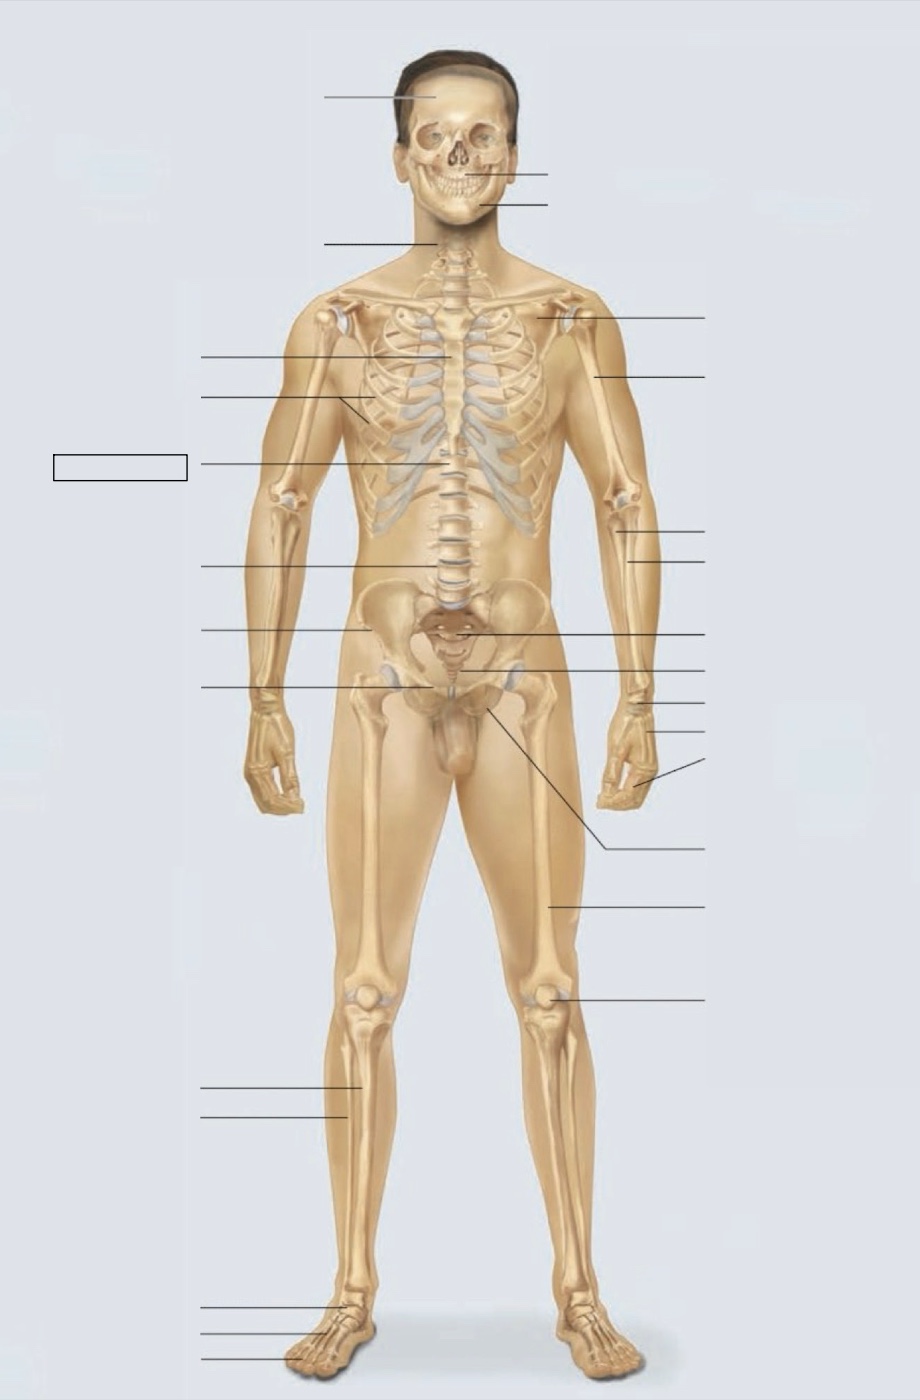

maxilla

mandible

scapula

humerus

ulna

radius

sacrum

coccyx

carpals

metacarpals

phalanges

ischium

femur

patella

phalanges

metatarsals

tarsals

fibula

tibia

pubis

ilium

lumbar vertebrae (L4)

thoracic vertebrae (T11)

ribs

sternum

cervical vertebrae

skull